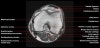

무릎 관절의 MRI 단면영상2016-08-31카테고리 106원본 보기1. Sagittal section 2. Coronal section 3. Axial section ← 이전 글전방 족근관증후군(Anterior tarsal tunnel syndrome) : 발등이 꽉 끼는 구두를 신은 후부터 발등을 누르면 아프고 엄지와 검지 발가락 사이가 저려요다음 글 →흉곽출구증후군(Thoracic outlet syndrome) : 팔이 아프고 감각이 떨어지면서 저려요같은 카테고리 글2017-06-10톰슨 검사(Thompson test) : 아킬레스건 파열을 조사하는 테스트2017-06-09Apley 압박 검사(Apley compression test) : 반월상 연골 손상을 조사하는 테스트2017-06-08맥머레이 시험(McMurray test) : 반월상 연골 손상을 조사하는 테스트← 전체 글로 돌아가기